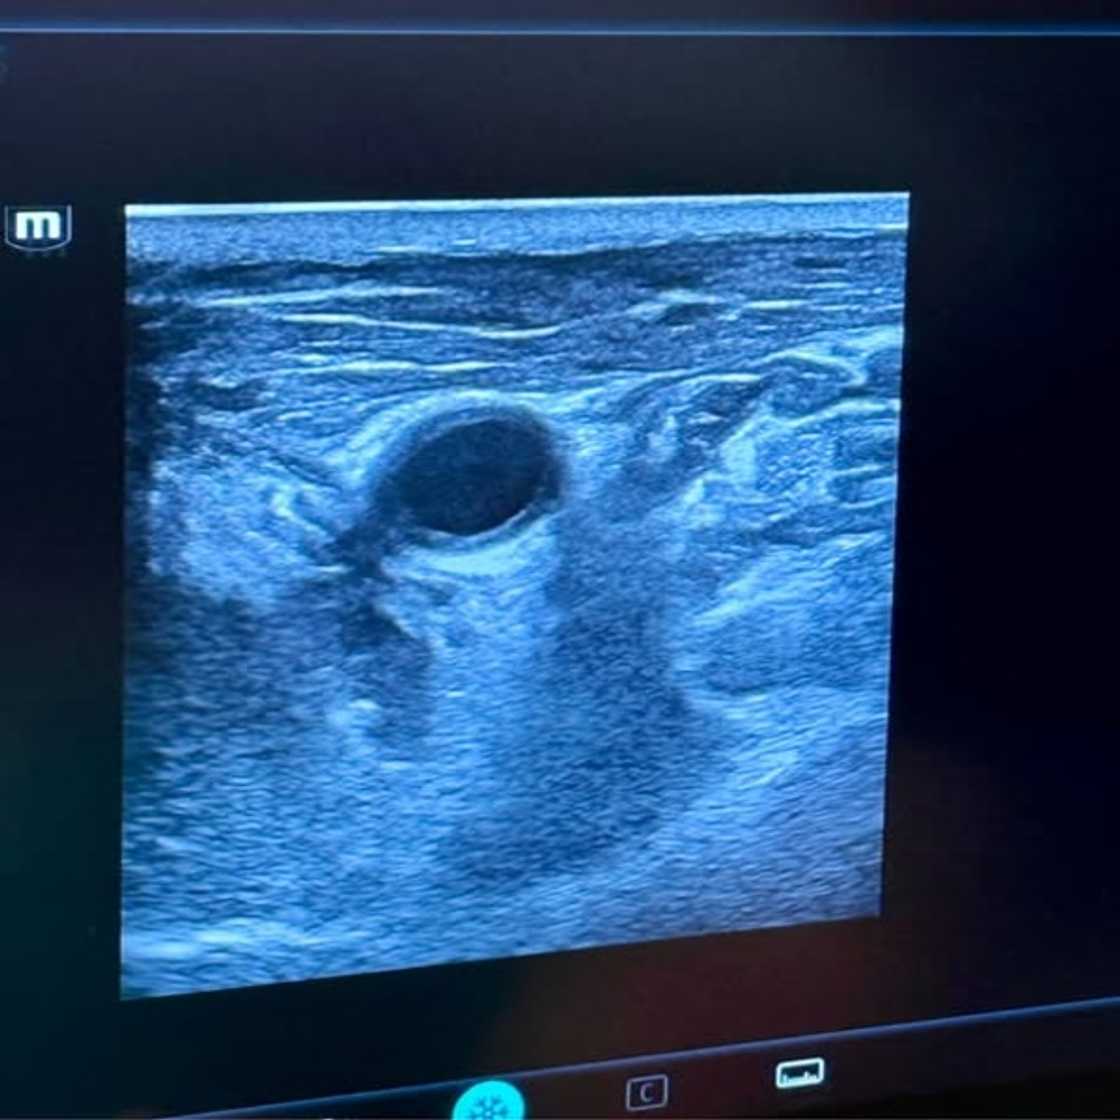

On 25 March 2026, a team at Netcare University of Cape Town Private Academic Hospital made medical history. Dr Gercois Human led a group of specialists who used cryoablation to treat Horn’s recurring thyroid cancer for the first time locally. The tumour had grown dangerously close to his windpipe, making further surgery far too risky for any surgeon to attempt.

“Because my neck had so much scar tissue, a traditional surgeon would have struggled to even see the tumor. Combined with its position right next to the trachea, further surgery was deemed too dangerous to pursue,” Human said.